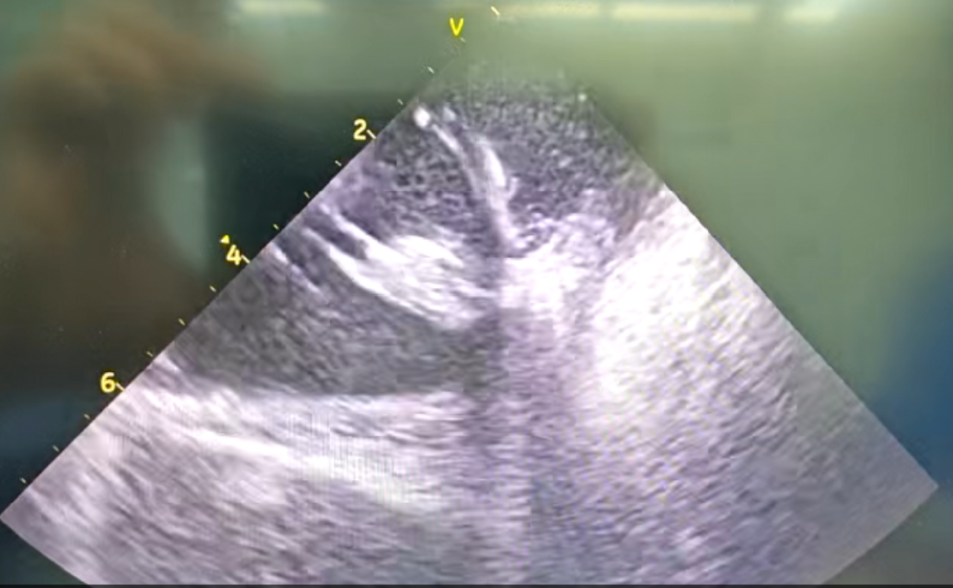

干穿心包进入外膜标测

心外膜基质

王林林主任医师谨慎操作,成功进入心外膜达到病变位置。术中,患者反复自发多形态室速,且转为室扑,同时出现血流动力学不稳定,需多次电除颤方能终止发作,标测难度极大。这就要求医疗团队必须在有限的标测时间内精准定位室速消融靶点,并结合心内外膜基质特征制定消融策略。经针对性消融后,患者未再自发室速,且室性早搏转为单一形态,经判定为右心室乳头肌来源,随即予以一并消融。术后经心室程序电刺激验证,室速未再被诱发。